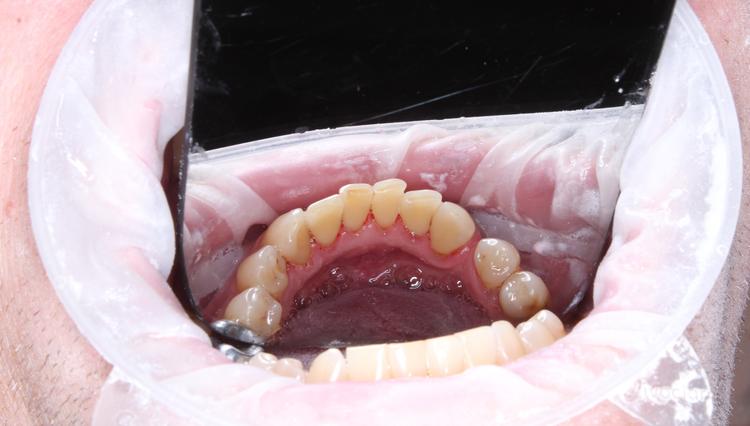

Профессиональная гигиена верхней фронтальной группы зубов

Во время процедуры удален пигментированный зубной налет и камень, проведена полировка зубов. После снятия зубных отложений можно оценить состояние зубов: видна старая пломба и кариозная полость.